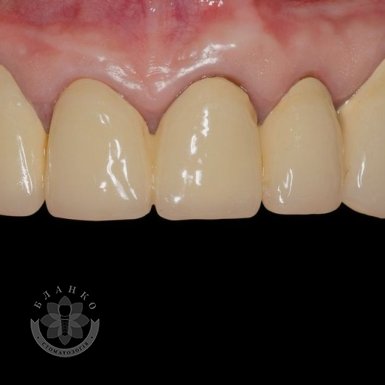

Зубная имплантация — это современное и надежное решение для восстановления утраченных зубов. В стоматологической клинике Бланко мы предлагаем имплантацию зубов «под ключ», что означает полный комплекс услуг — от диагностики до установки коронки, без скрытых платежей и неожиданных расходов.

🔹 Высококачественные импланты – используем только проверенные бренды, которые служат десятилетиями.